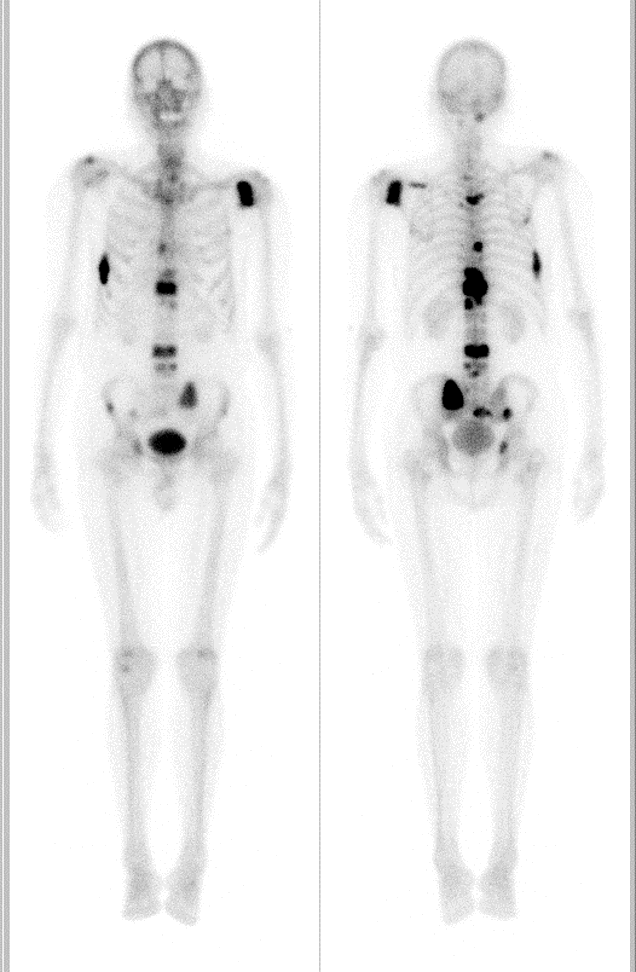

Radioisotope bone scan showing metastases